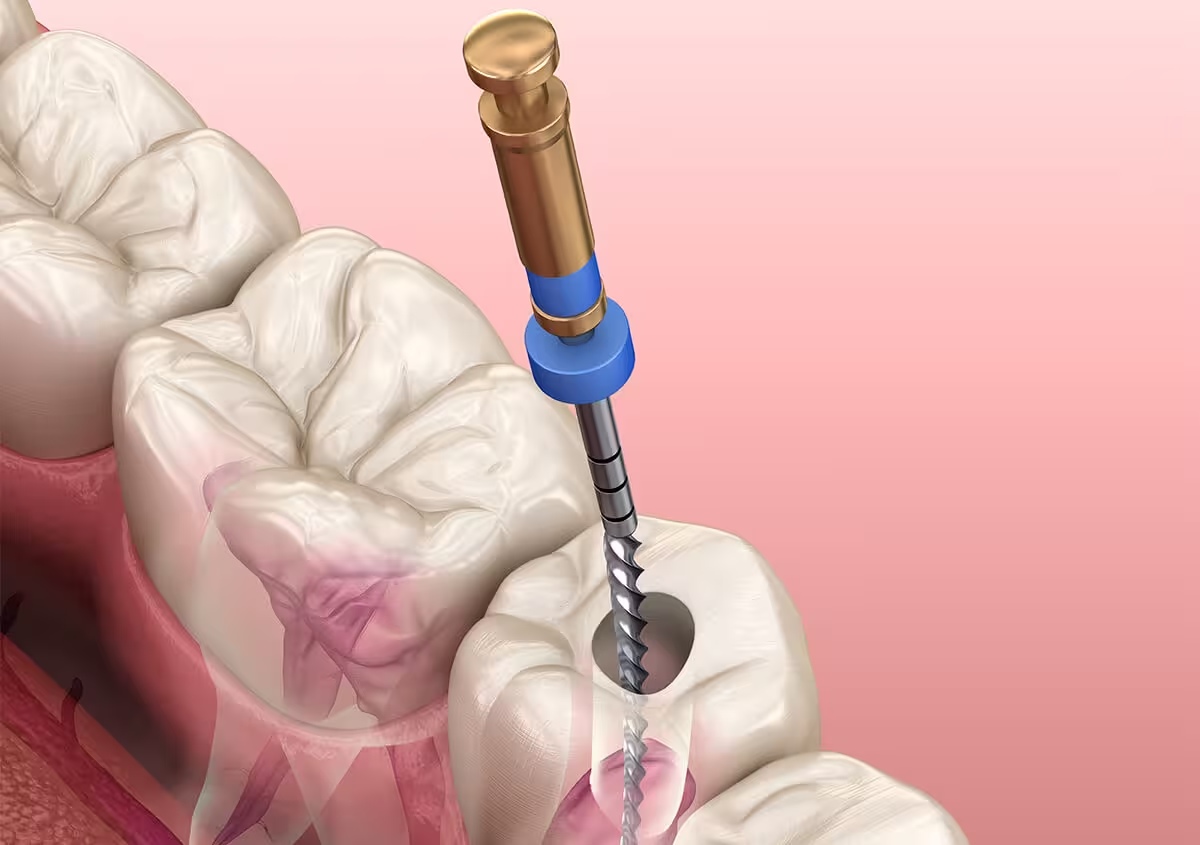

Emergency Root Canals

At Podder Dental Clinic, we provide urgent emergency root canal treatments to relieve severe tooth pain caused by infection or inflammation deep within the tooth’s pulp. When a toothache becomes intense or is accompanied by swelling, sensitivity, or abscess, prompt endodontic therapy can save the tooth and prevent the infection from spreading. Our experienced dentists use advanced tools and local anesthesia to perform the procedure quickly and comfortably, often on the same day you call. Emergency root canals not only alleviate pain but also preserve your natural tooth, avoiding extraction and more extensive treatment later. With compassionate care and timely intervention, we ensure you get fast relief and long-term dental health restoration.